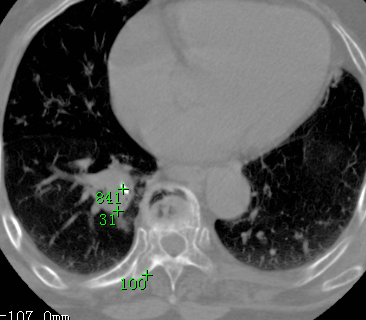

标题: CT26680:肺部右下肺静脉干结节的界定 [打印本页]

标题: CT26680:肺部右下肺静脉干结节的界定

经追查说有支扩咯血病史,但不确定

考虑1、周围型肺癌,2肺静脉畸形,前者可能大,建议增强检查。

考虑1、周围型肺癌,2肺静脉畸形,前者可能大,建议增强检查。支持!

不排除右肺下叶周围型肺癌可能。